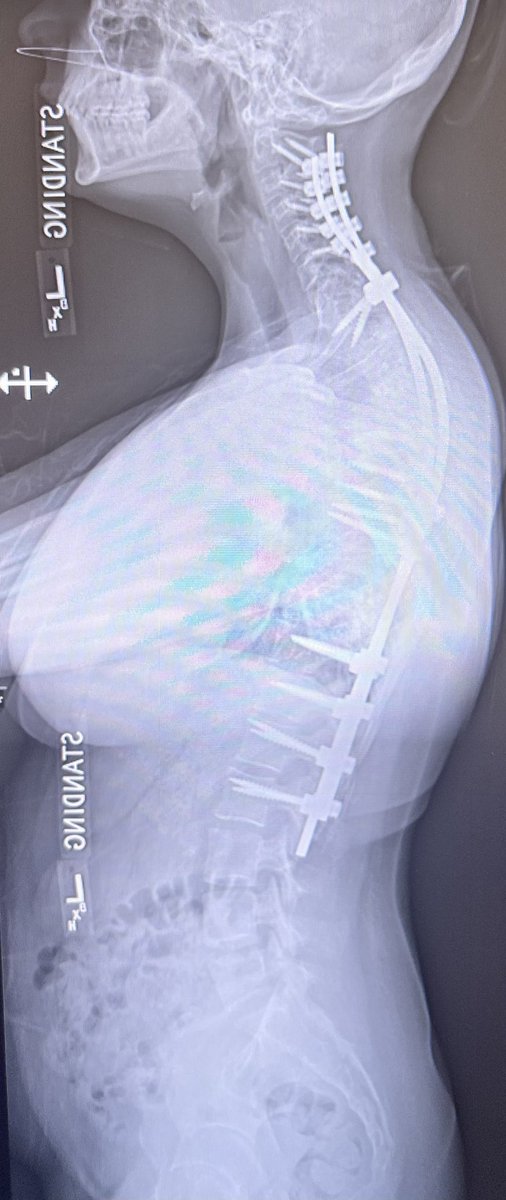

Pre-and post-op awake MIS fusion to correct this patient scoliosis. @mayoclinic our associate surgeon @RodNavarroMD work hand in hand to learn the latest approach, enabling technology and freehand. Accepting applications for 2024-2025. @DoctorQMd @oakinduroMD @wchrisfox

Very satisfying case not only because of the deformity correction we achieved but more importantly because of the impact this surgery had on the patient’s life. @MayoClinicNeuro patient specific 3D printing for planning. https://t.co/Nz6Yehvu7Y! For new appointments #scoliosis